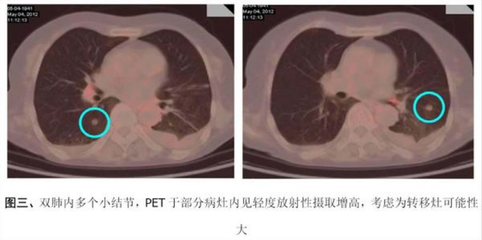

直径大于3cm的局部病灶称为肺部肿块,肺癌的可能性比较大,不在本共识范围内。一般认为> 10个弥漫性结节很可能伴有症状,可由胸外恶性肿瘤转移或活动性感染引起,原发性肺癌的可能性相对较小。第二,肺部小结节不代表早期肺癌。肺部很多疾病都会形成结节,如炎症、结核、霉菌、亚段肺不张、出血等。所以肺部小结节病变的可能诊断可以说是多种多样的,包括炎性假瘤、错构瘤、结核瘤、真菌感染、硬化性肺细胞瘤等等。